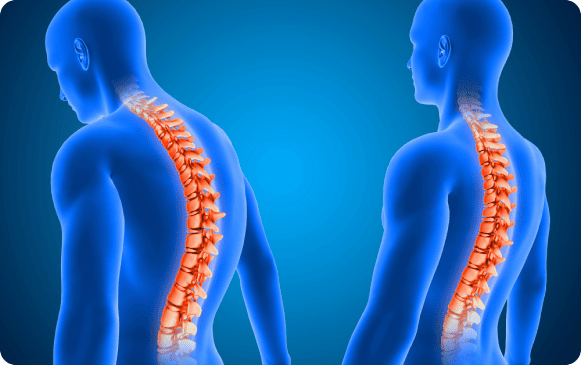

What is Spine Surgery?

Spine surgery is necessary for certain back pain cases to prevent complications or improve quality of life. It treats various spine conditions such as herniated discs, scoliosis, and spinal fractures, using the latest surgical methods to ensure effective recovery and long-term relief.

Scoliosis: A sideways curvature of the spine that can result from congenital factors, neuromuscular conditions, or osteoporosis. Treatment varies based on age, severity, and type, ranging from observation to braces or surgery in severe cases.

Congenital Spine Deformities: Present at birth due to abnormal vertebral development. Treatment focuses on preventing progression through braces or surgery for more severe cases like kyphosis and lordosis.